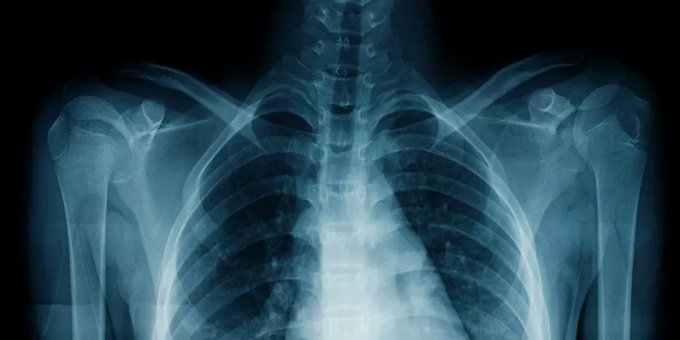

An AI used medical notes to teach itself to spot disease on chest x-rays

After crunching through thousands of chest x-rays and the clinical reports that accompany them, an AI has learned to spot diseases in those scans as accurately as a human radiologist.

A team of researchers from Harvard Medical School trained the CheXzero model on a publicly available data set of more than 377,000 chest x-rays and more than 227,000 corresponding clinical reports. This taught it to associate certain types of images with their existing notes, rather than learning from structured data that had been manually labeled for the task.